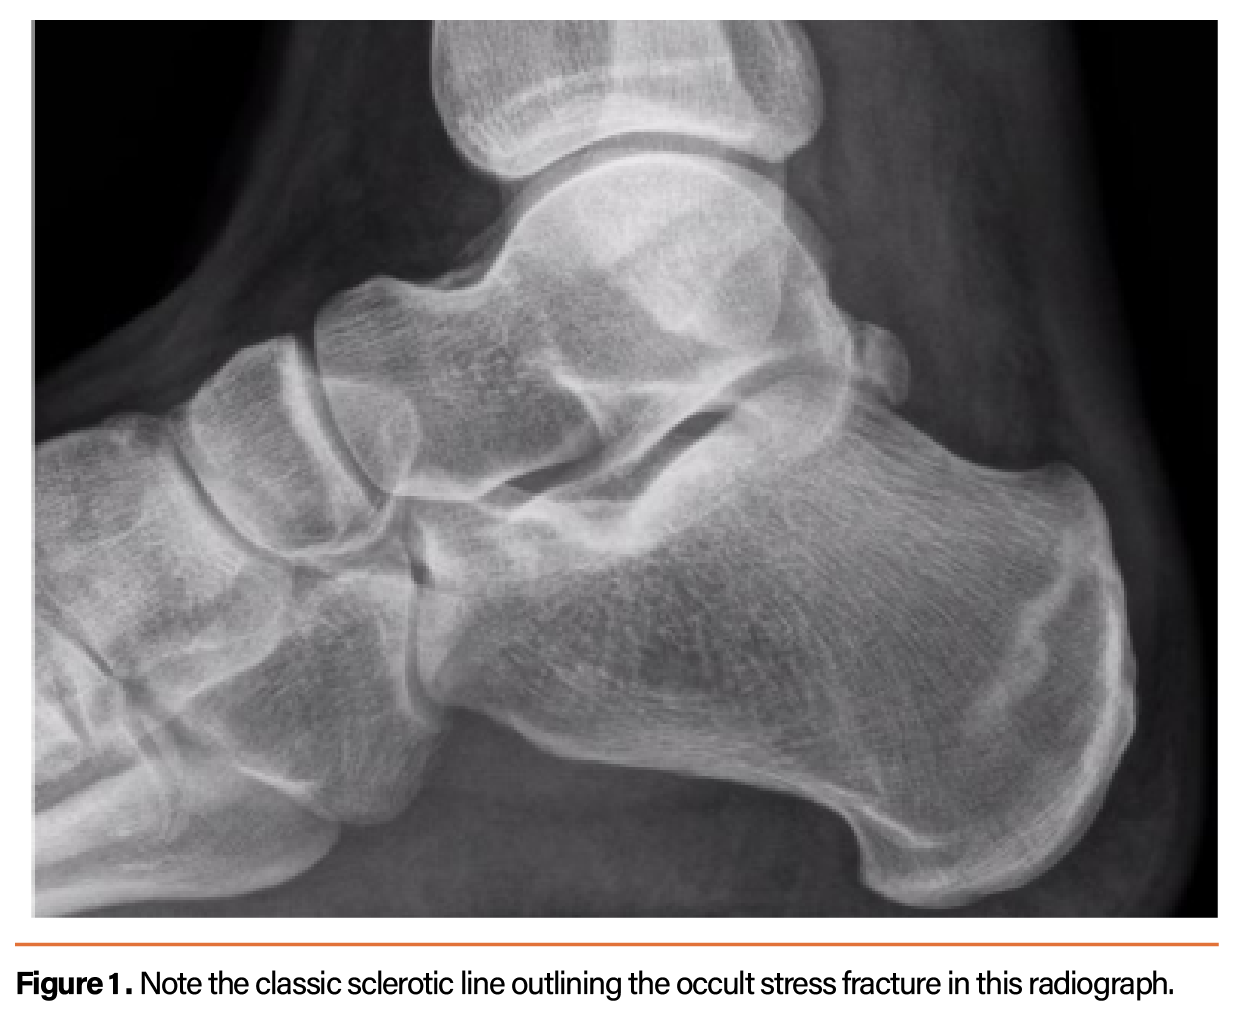

TitleFacet Joint Syndrome / Arthritis